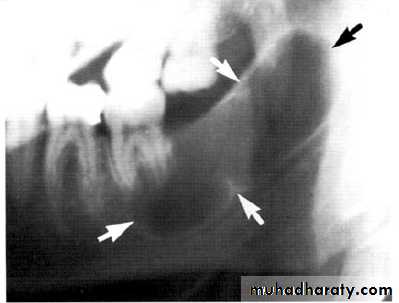

• Aneurysmal Bone Cyst

Large multilocular aneurysmal bone cyst

in the ramus with marked expansion andthe displacement of/8.

It is non-neoplastic ,exaggerated , localized, proliferative lesion of vascular tissue, containing giant cells.

It’s a variation of the central giant cell granuloma , can be diagnosed only by histological examination